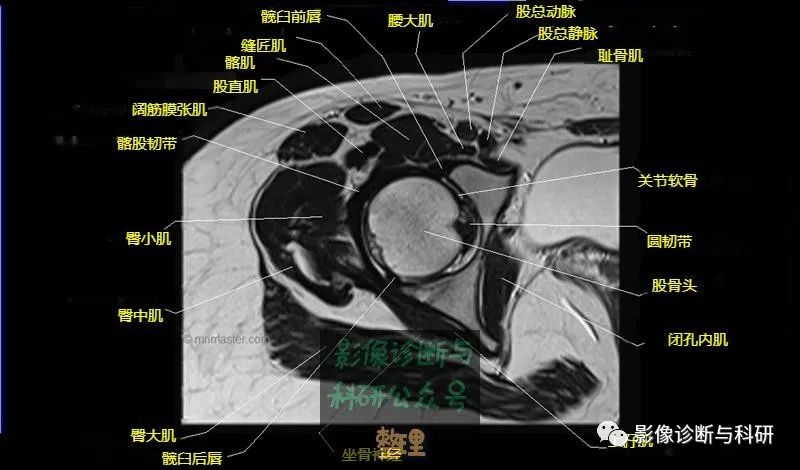

髋关节MR轴位详细标注

大腿肌配布于股骨周围,分前、后和内侧三群

前群

位于大腿前面,有缝匠肌和股四头肌。

内侧群

位于大腿内侧,共5块,其中股薄肌位于最内侧;另4块分三层,浅层靠外上方为为耻骨肌,下方为肌长收肌。长收肌深面是第二层的肌短收肌。第三层是强有力的大收肌。这一群肌均起自耻骨支和坐骨支,除股薄肌止于胫骨上端内侧外,其余各肌都抵止在股骨粗线。

后群

位于股骨后方,包括股二头肌、半腱肌和半膜肌。